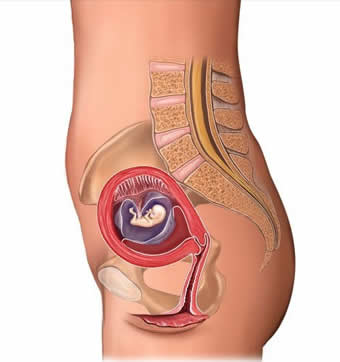

怀胎十月,辛苦的孕妈们期间要经受各种孕期妊娠反应,孕期呕吐、手脚水肿、脚抽筋等等“折磨”后才能顺利健康产下宝宝。从一个小小的受精卵到发育成完整的胎儿,每个月胎儿都在以妈妈们想不到的速度在成长。胎儿在妈妈腹中是怎么一步步发育呢?这些可是孕产医生都不会给你详细解说,下面让我们一起来直击胎儿每月的发育过程。

一个月胎儿身长约0.2厘米,体重约1克。受精卵经过3-4天的运动到达子宫腔,在这过程中由一个细胞分裂成多个细胞,并成为一个总体积不变的实心细胞团,称为桑胚体。这个时期你自身可能还没有什么感觉,但在你的身体内却进行着一场变革。到了第4周,着床后的胚胎慢慢长大,这时大脑的发育已经开始,受精卵不断地分裂,胎儿的中枢神经系统脑、心脏开始发育。

胎芽的身长约2.3厘米,重量约4克左右。长长的尾巴逐渐缩短,头和躯干也能区别清楚,眼睛、耳朵、嘴也大致出现了,已经像人的脸形了。手、脚已分明,甚至5个手指及脚趾都有了,手指和脚趾间看上去有少量的蹼状物。胃、肠、心脏、肝脏等内脏已初具规模,特别是肝脏在明显地发育。神经管鼓起,大脑急速发育。从外表还分不出性别,但内外生殖器的原基已经能被辨认。胎芽的身长约2.3厘米,重量约4克左右。

胎儿的身体为7-9厘米,体重约20克。现在,胎儿头部的增长速度开始放慢,而身体其他部位的增长速度逐渐加快了。手指和脚趾已经完全分开,部分骨骼开始变得坚硬,并出现关节雏形。胎儿维持生命的器官已经开始工作,如肝脏开始分泌胆汁,肾脏分泌尿液到膀胱。胎儿身体的姿势变得不那么弯曲而是更直了。这时,从外表可以清楚地区分性别了内生殖器分泌机能也活跃起来。脐带也渐长了,胎儿可以在羊水中自由转动。

身长18厘米,体重120克左右。由于胎盘长出,改善了母体供给胎儿的营养,胎儿的成长速度加快。胎膜结实了,羊水的数量也从这个时期开始急速增加。心脏的搏动也更加活跃,内脏几乎已形成。此外,胎儿的胎膊、腿能稍微活动了,这是因为骨头和肌肉发达,长结实了的缘故。

身长18一22厘米,体重250 -300克。头已占全身长的1 /3,并有明显的胎动。胎儿的骨骼和肌肉开始发育,皮下脂肪开始沉着,但还比较少,肢体活动能力增强。胎儿已会吞咽羊水,把羊水吞进后通过肾脏过滤,变成洁净的尿液重新排入羊水中。随着骨骼和肌肉的健壮,胳膊、腿的活动活跃起来,这时会感到明显的胎动。心脏的活动也活跃起来,可以听到强有力的心音。

身长28-34厘米,体重约660克了。大脑继续发育,大脑皮层已有六层结构,沟回增多。胎儿面目清楚,头发、眉毛、睫毛等清楚可见。胎儿皮下脂肪继续蓄积,但进展不大。皮肤呈皱缩状,表面开始附着胎质。骨骼已相当结实了,如采用X钱摄片,能清楚地看到头盖骨,脊椎、肋骨、四肢的骨骼等,关节也在这个时期开始发达。

身长为35-38厘米,体重为l000克,脸也像人了,尽管这么说,但由于皱纹很多,相貌却象个老人似的。胎儿大脑知觉和运动开始发达,动作能够自控,脸部有表情,听觉反应.能力充分,出现记忆、意识萌芽.头发已长出5厘米左右。眼睑分界清楚可见,眼睛已能睁开。外生殖器中,男孩子的睾丸还没有降下来,但女孩子的小阴唇,阴核已清楚地突起。吸乳的力量还不充分,气管和肺部还不发达。

身长为40-44厘米,体重达1500克左右。从这时起,羊水量不再象以前那样增加了。一直自由转动的胎儿,到了这个时期,位置也固定了,由于头重,一般头部自然朝下。胎儿对外界的强烈影响也有反应。胎儿的嗅觉、味觉和视觉已具功能。肺、肾、胃等重要器官发育完成,但器官功能还较差。

身长为45-48厘米,体重增加了1000克左右,大约2500克了。胎儿听觉敏感,意识进一步发展,可有喜、怒等表情,内脏发育齐全、成熟,性器官发育完成,男宝宝辜丸下降,女宝宝大阴唇隆起。皮下脂肪增加,全身变得圆润,皮肤皱纹减少,胎儿已具备呼吸、吸吮等生活能力。

身长为48-50厘米,体重为3000克左右。皱纹已消失,变成个淡黄色的胖乎乎的胎儿,头盖骨变硬,指甲也长到超出手指,头发长2-3厘米。以心脏、肝脏为首的循环、呼吸、消化、泌尿等器官已全部形成,已经可以在体外独立生活了。还有胎儿的头部,已进入母体的骨盆之中,身体的位置稍有下降,胎动比以前更加频繁。